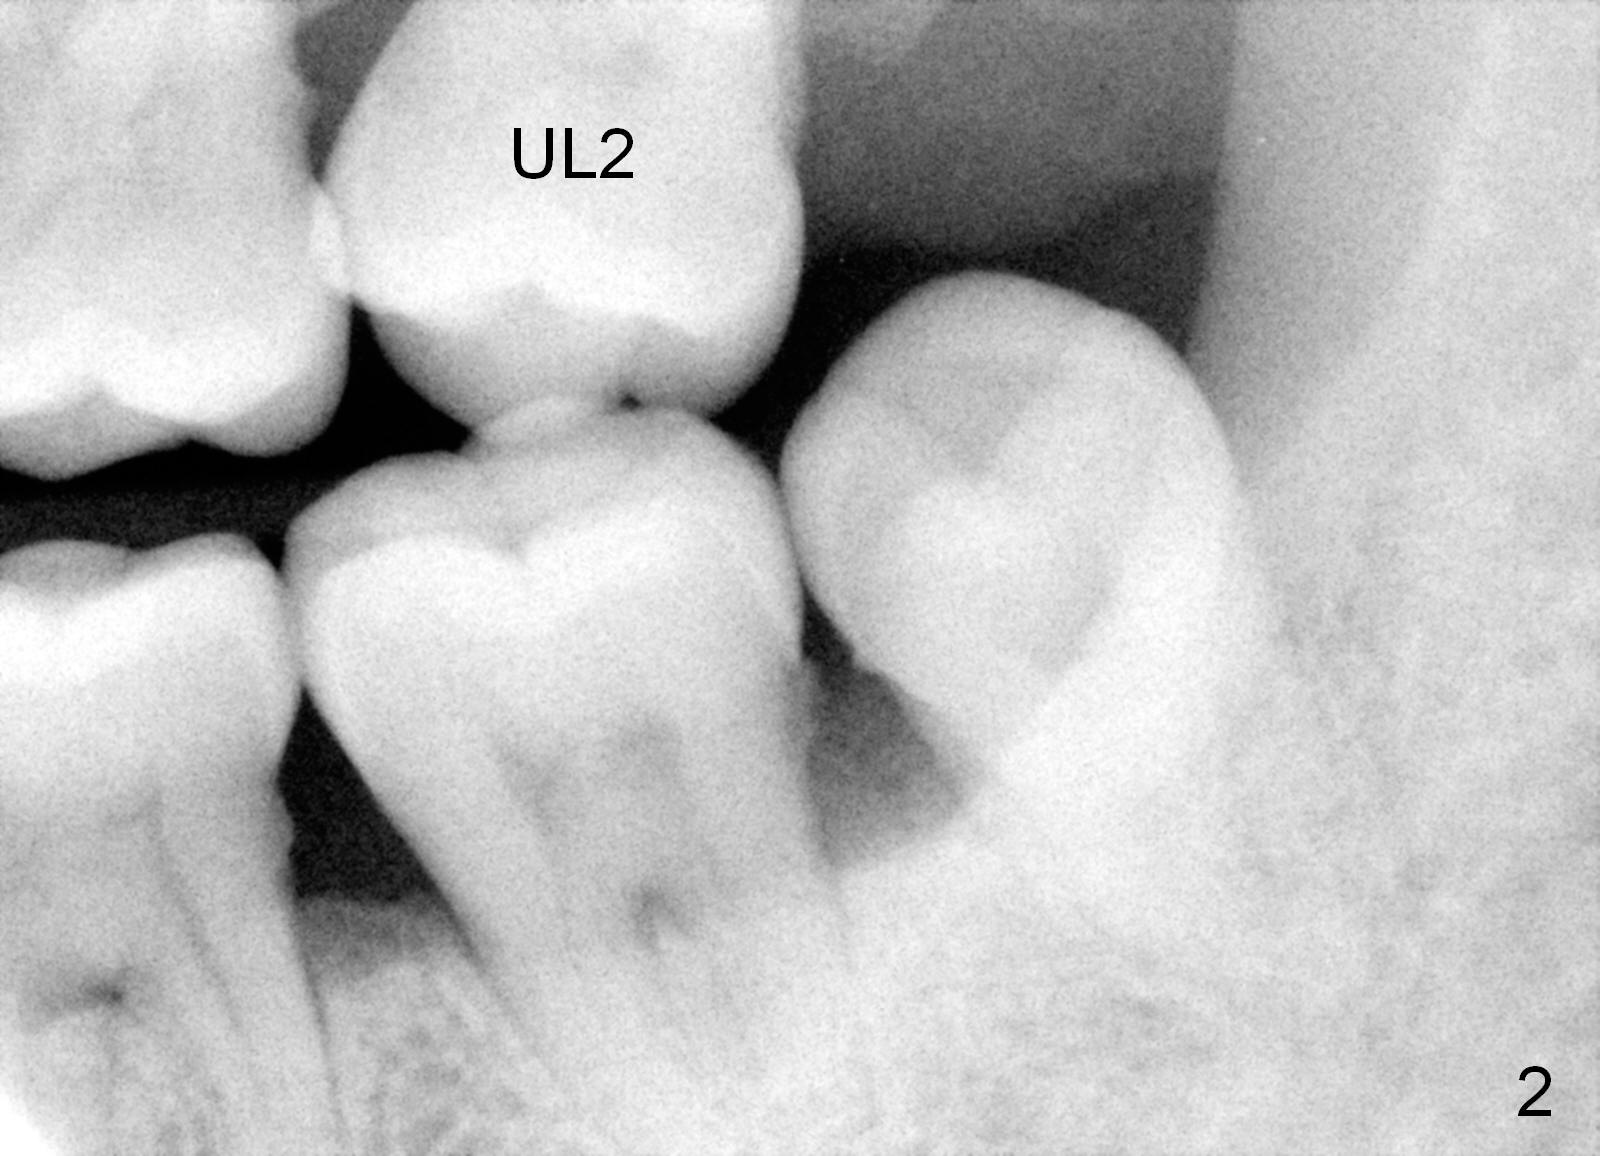

A 49-year-old lady is scared of dentistry. She presented with chronic periodontitis 7 years ago. The lower right 2nd molar had been missing (Fig.1 LR2), while the upper right 2nd molar shifted distally (arrow). Her chief complaint was mobility of #15 (Fig.2,4 UL2 with severe bone loss (*)). The tooth was extracted with expectation of return for implant placement in 6-8 weeks.

When she returns 7 years later, the tooth #2 has perio abscess with severe bone loss (Fig.3). She refuses to take antibiotic for infection control, but agrees to have immediate implant for #2 because of 1-staged surgery (Fig.5 I: 8x17 mm; A: abutment; P: bone powder (graft)). She is aware of delayed implants at the sites of #15 and 31 later. The bone height at the site of #15 reduces from 12 mm (Fig.4) to 7 mm (Fig.6) in 7 years.